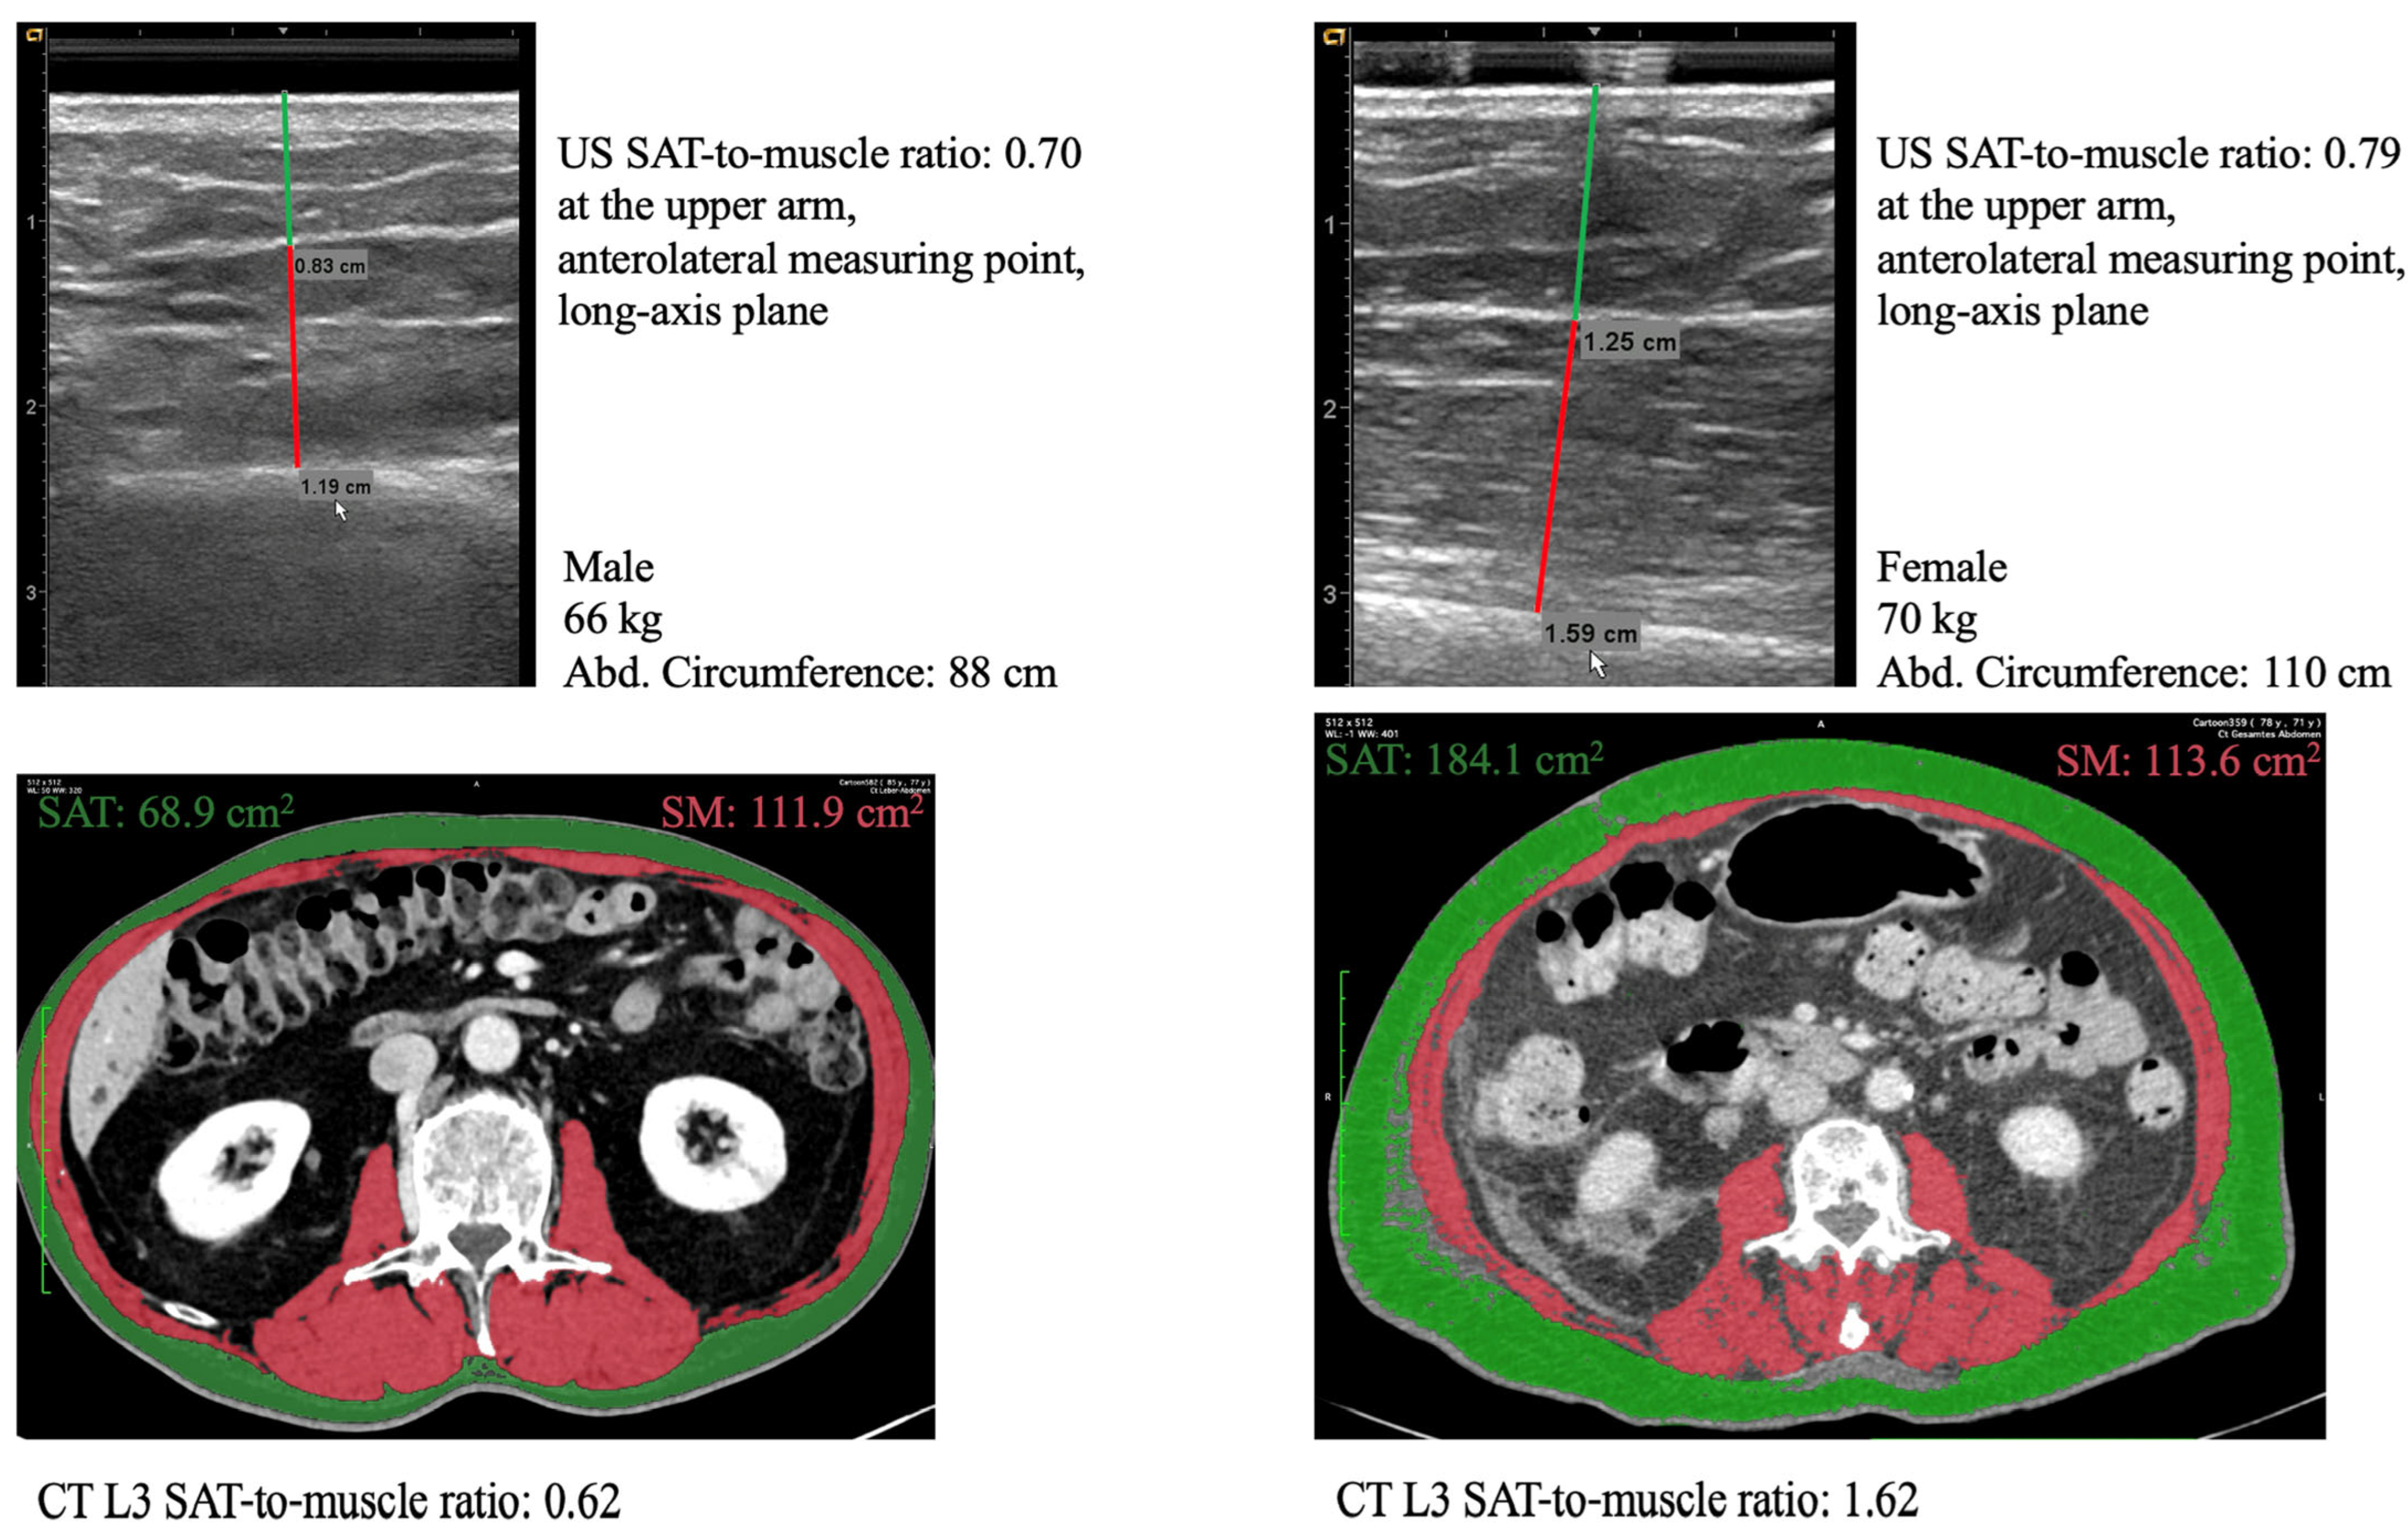

| anterolateral s-a | 0.70 | (0.45–1.02) | 0.54 | (0.41–0.78) | 0.98 | (0.68–1.33) | <0.001 | |

| anterolateral l-a | 0.71 | (0.47–1.09) | 0.57 | (0.42–0.80) | 1.06 | (0.69–1.43) | <0.001 | |

| SAT-to-muscle ratio (SAT area/SM area) | 1.08 | (0.65–1.67) [0.01–4.71] | 0.86 | (0.59–1.28) [0.01–2.98] | 1.51 | (1.01–2.20) [0.14–4.71] | <0.001 | |